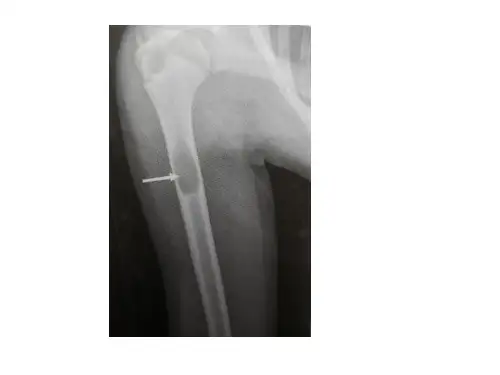

二、影像学表现1.X线表现动脉瘤样骨囊肿的X线表现可分为骨质破坏型和无骨质破坏型两种类型。

骨质破坏型表现为囊状骨破坏区,边缘呈不规则或波浪状,可有骨质硬化或壁内分隔。

无骨质破坏型表现为周围骨质增生,并伴有骨膜反应。

X线检查可见溶骨性病变,病变边缘有狭窄的硬化带或者不规则小梁。